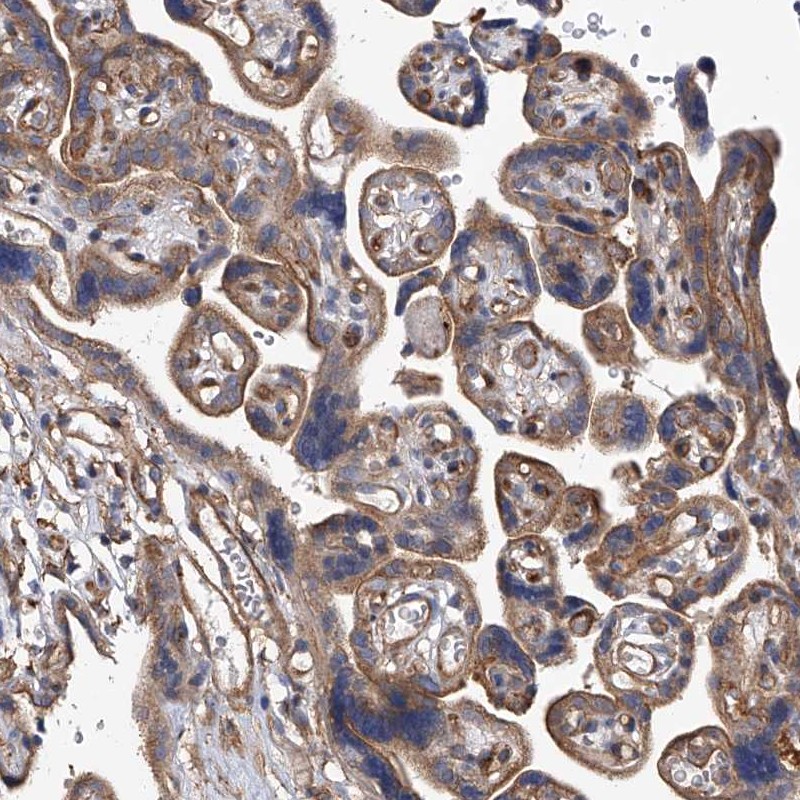

Immunohistochemical staining of human placenta shows cytoplasmic positivity in trophoblasts.